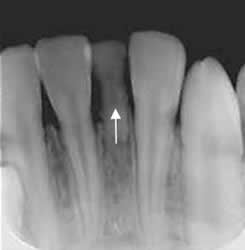

Fig 81. Mesiodens.

Rx periapical. Diente supernumerario, mas pequeño, entre ambos incisivos mediales, que corresponde a mesiodens.